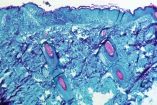

La viruela del mono, también conocida como "monkeypox", es una enfermedad zoonótica viral causada por el virus de la viruela símica.